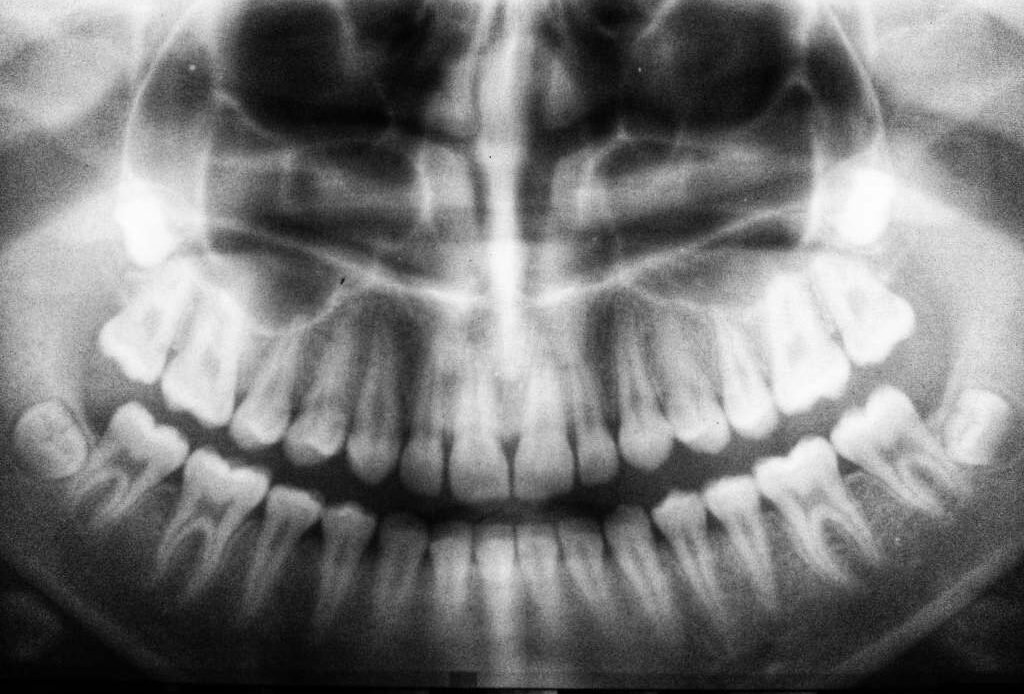

Medicines dedicated to improving a specific condition and resulting in side effects create concern. The FDA 2022 released a safety communication regarding severe dental health issues, like tooth loss, cavities, oral infections, and tooth decay, occurring in people who used Suboxone Sublingual Film, a buprenorphine medication. These patients have filed legal claims against Indivior, the drug manufacturer.

Suboxone Sublingual Film is a medicine that has been used to treat opiate addiction. In the past few months of 2023, the number of lawsuits for Suboxone dental decay has gone up. Almost all plaintiffs shared that they faced permanent tooth loss and dental damage that led to other expensive treatments and reduced their quality of life.

It’s this change that has made more users experience dental side effects. The reports include the following:

- Tooth extractors

- Several dental decays

- Chipped or cracked teeth

- Tooth loss